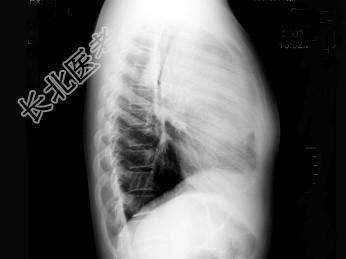

- 单项选择题女,13岁, 发热、乏力数天,X线检查如图, 最可能的诊断是 ( )

A、胸腺瘤

B、淋巴瘤

C、畸胎瘤

D、间皮囊肿

E、神经源性肿瘤